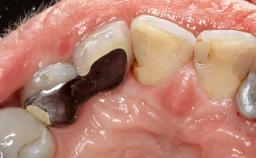

Treatment of Peri-Implant Mucositis at a Zirconia Implant

Recent clinical studies, most with short-to-medium term observation periods, have reported on the favorable clinical performance of zirconia implants in terms of survival rates, clinical, and radiographic outcomes (Roehling and coworkers 2016; Roehling and coworkers 2017; Rodriguez and coworkers 2018; Lorenz and coworkers 2019). Nonetheless, a rather high incidence of peri-implant disease at zirconia implants (39% of implants) was noted throughout a two-year period, highlighting the need for treatment protocols of peri-implant diseases at zirconia implants (Becker and coworkers 2017).